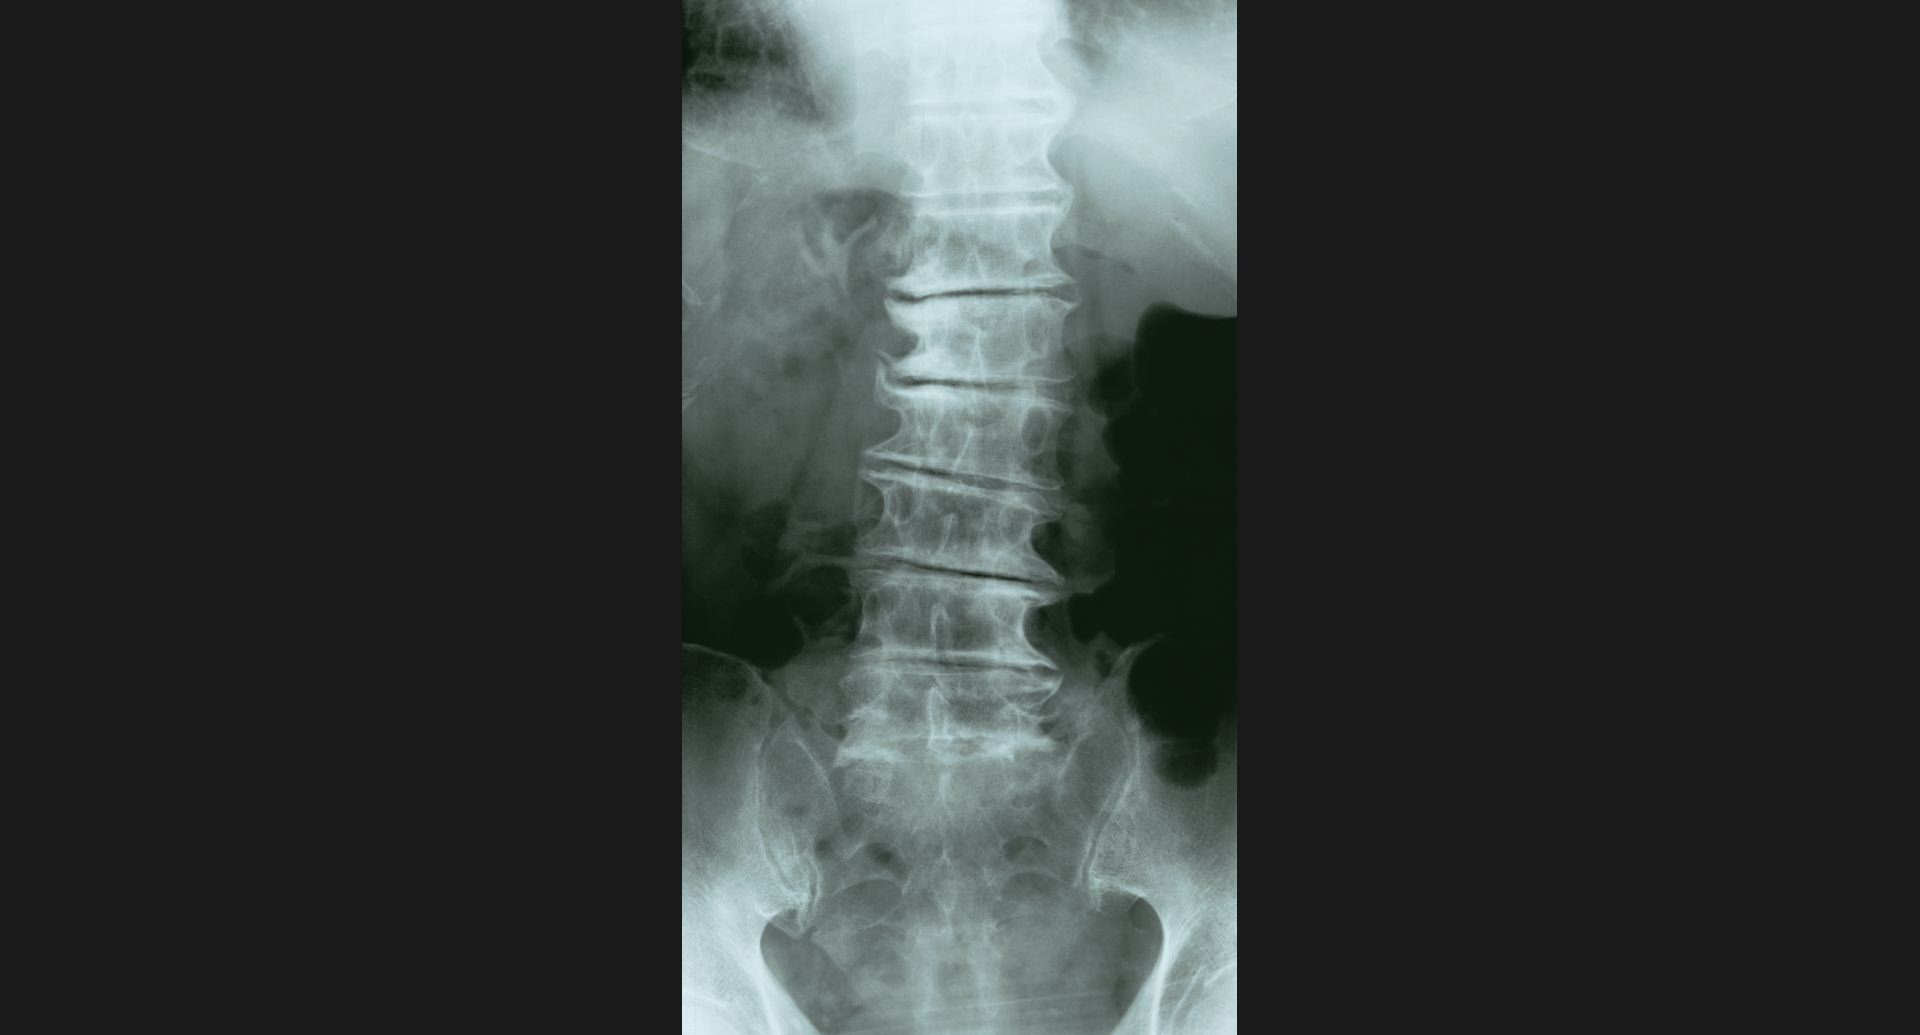

fig.14(77KB) :Phantom disc

disc内の透亮像。spur。